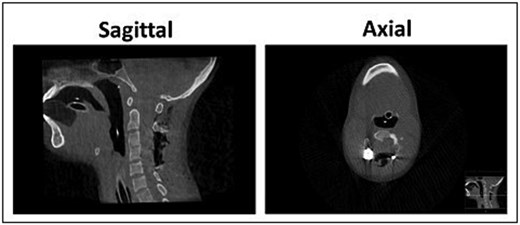

Stabilization was achieved via posterior fixation using bilateral C2 pedicle screws and C3–C5 lateral mass screws connected by rods. Decortication was performed, and an allograft was applied to promote fusion. Following decompression, neuromonitoring detected a complete loss of left-sided Motor evoked potentials (MEPs) and Somato-sentory evoked potentials (SSEPs). However, microscopic inspection revealed no mechanical trauma or dural tear. Adequate decompression and hardware placement were confirmed via intraoperative CT (Fig. 3).

Post-operative CT scan of the cervical spine demonstrating post-operative adequate decompression and alignment, with canal dimensions increasing from a minimal preoperative size of 4.7 × 12.1 mm (Anterior-Posterior*BiLateral) to 27.3 × 17.7 mm at the level of upper 1/4 of C4.